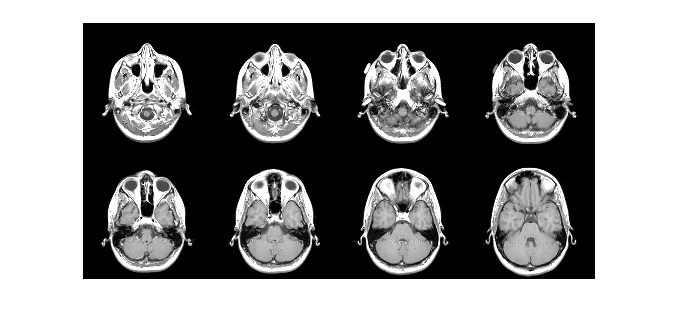

Combine multiple image frames into one rectangular tiled image

By default, the imtile function arranges the images so that they

roughly form a square. You can change the arrangement using optional name-value arguments.